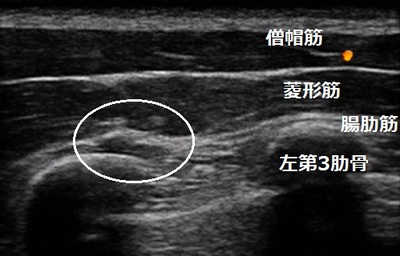

左肩上部 右肩上部

首や肩、背中の筋肉が全体的に硬くなっています。両肩の痛い箇所を指で押すとコリコリした部分を触知

します。その部分を超音波観察すると筋肉と筋膜や筋肉の一部が硬く癒着していました(画像丸の囲み)。

硬く癒着した筋肉などは放っておいても自然に柔軟になりません。軟部組織の癒着を丁寧に取り除く

リリース治療を行います。